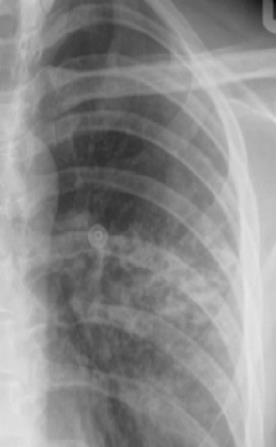

Analise a radiografia, abaixo, de um paciente portador de Sarcoidose:

Fonte: https://www.revistas.usp.br/rmrp/article/download/154795/156960/374834

A opacidade demonstrada caracteriza padrão:

Provas